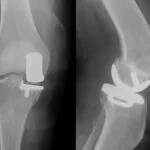

I have had 2 knee replacements within one year. Paul, Mark, and Cole have all helped in getting my knees back to where I can do most anything I want to do. I am bike riding, hiking, and working out at the gym, pretty much the same as before. I highly recommend BTPT for their skills and their welcoming.

In January 2016 & January 2018 I had my knees replaced in 2016 – right knee & 2018 –left. I worked with Paul for my recovery. I was luck to have easy recoveries, I bounce back quickly. But I also respect both Paul and Cole and their experience. I would recommend either of them to all my friends!

I had partial knee replacement surgery in the Fall of 2017. My surgery itself went well, however, as a result of the antibiotics administered while in surgery I obtained C-Diff, a very contagious ailment. As a result, I was quarantined and couldn’t start my PT until a month later then scheduled. When I first started with Cole, I could hardly move my leg: upon constant PT and Cole using his expertise, I’m doing remarkably well. I’m so grateful to BTPT.

Over the past 6 months I have had 2 knee replacements on my right leg. After the first surgery my doctor suggested I go to Bridle Trails PT. I worked with Cole, who worked diligently to get me up and dancing again. However, after several months of hard-work, we learned of an old injury that was causing issues. The only way to fix the problem was to put in a different knee. Between the old injury and 4 months of being laid up, I wasn’t just back to square one, it almost felt like I was having to learn to walk again. Needless to say, I was having a hard time dealing with the setback, and was very disheartened.

In October I had a knee replacement. They told me to have therapy. I had no idea where to go. I looked in the phone book and picked BTPT. I’m glad I did. I’ve had good treatments. I thank them for all the help I got!